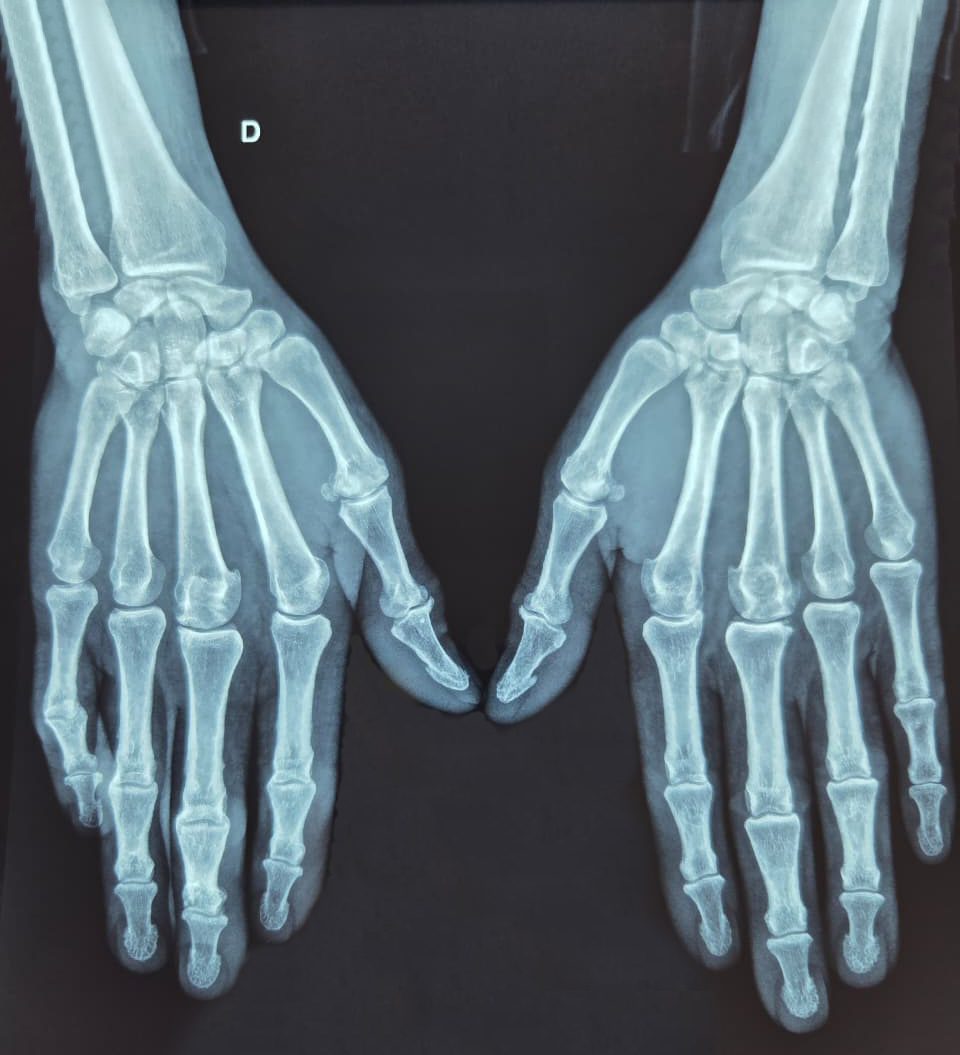

À l’examen : tuméfaction ferme des 2e et 3e articulations métacarpophalangiennes (MCP) bilatérales ; absence de synovite franche ; pas d’atteinte notable des interphalangiennes distales. Le bilan inflammatoire est normal. Le facteur rhumatoïde et l’ACPA sont négatifs. Une radiographie standard des deux mains est réalisée.

L’arthrose primitive des mains touche préférentiellement les interphalangiennes distales (nodules d’Heberden) et la base du pouce (rhizarthrose). L’atteinte prédominante des 2e et 3e MCP est inhabituelle. De plus, les ostéophytes en crochet observés ici ne correspondent pas aux ostéophytes marginaux classiques de l’arthrose commune.

La chondrocalcinose peut toucher les poignets et les MCP et peut mimer une arthropathie dégénérative. Cependant, l’atteinte sélective et marquée des 2e et 3e MCP associée à des ostéophytes en crochet est beaucoup plus caractéristique d’une arthropathie liée à une surcharge martiale. Par ailleurs, le terrain métabolique (diabète, cytolyse) renforce l’hypothèse d’une hémochromatose sous-jacente.

L’hémochromatose est une maladie génétique autosomique récessive, le plus souvent liée à une mutation du gène HFE, responsable d’une hyperabsorption intestinale du fer et d’une surcharge progressive des organes. Le dépôt excessif de fer entraîne un stress oxydatif responsable d’atteintes hépatiques, pancréatiques, cardiaques, endocriniennes et articulaires. L’arthropathie est souvent révélatrice et se caractérise par : une atteinte précoce des MCP 2 et 3 ; des ostéophytes en crochet évocateurs ;une possible association à une chondrocalcinose. Chez ce patient, l’atteinte prédominante des 2e et 3e MCP à la radiographie est l’élément sémiologique clé. Le diagnostic biologique repose sur une élévation de la ferritine et un coefficient de saturation de la transferrine > à 45 %. La confirmation peut être obtenue par étude génétique du gène HFE. Le traitement repose sur les saignées régulières visant à normaliser la ferritinémie et prévenir les complications viscérales (mais l’arthropathie peut continuer à évoluer).

Toute arthropathie prédominant aux 2e et 3e MCP avec ostéophytes en crochet doit faire évoquer une hémochromatose, même en l’absence de syndrome inflammatoire.